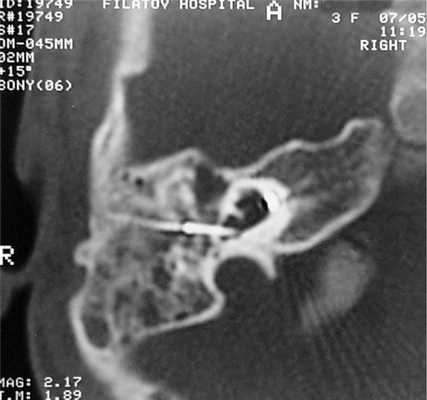

На КТ височных костей справа послеоперационная полость, заполненная мягкотканным образованием, определяется большой костный дефект в направлении сигмовидного синуса и мозжечка (рис. 2, а). Рисунок 2. КТ и МРТ височных костей больной У. с хроническим правосторонним средним отитом. Состояние после радикальной операции (1993 г.), санирующей операции с мастоидопластикой и тимпанопластикой (2003 г.). Холестеатома. Парез лицевого нерва. а — КТ; б — МРТ основания черепа в режиме Т1; в — в режиме Т2; г — в режиме non-EPI DWI.

Больной была выполнена МРТ (рис. 2, б—г).

В режимах Т2 и non-EPI DWI определяется сигнал высокой интенсивности, в режиме Т1 — низкоинтенсивный сигнал. Это может свидетельствовать о наличии холестеатомы мастоидальной полости и пирамиды височной кости. Диагноз: хронический правосторонний средний отит; состояние после радикальной операции в 1993 г. и санирующей операции с мастоидопластикой и тимпанопластикой в 2003 г.; холестеатома; парез лицевого нерва.

Больной произведена санирующая реоперация, в ходе которой удалена холестеатома больших размеров, заполняющая отшнурованную послеоперационную полость. Эта полость распространялась до верхушки сосцевидного отростка, граничила с твердой мозговой оболочкой и достигала верхушки пирамиды височной кости. Полость облитерирована. В послеоперационном периоде получен хороший функциональный результат. Ухо толерантно к воде, не было обострений, гноетечения, головокружений. Сохранилась кондуктивная тугоухость I степени. МРТ через 9 мес подтвердила отсутствие холестеатомы.